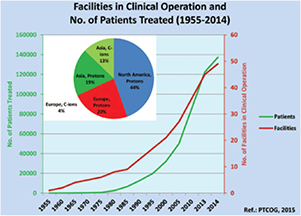

Radiotherapy is an essential component of cancer therapy. The combination of surgery, chemotherapy and radiotherapy is becoming a standard for most cancer patients. Out of the approximately 2/3 of cancer patients receiving radiotherapy, over 80% is irradiated with x-rays produced at linear electron accelerators (Linacs). The others receive specialized treatments such as gamma knife or brachytherapy. Only about 0.8% of the radiotherapy patients are treated with high-energy charged particles, but their number is rapidly increasing (figure 1). The rationale for using accelerated ions in therapy comes from the depth-dose distribution (figure 2), and was originally proposed by Wilson (1946), a student of Ernest Orlando Lawrence at the University of California in Berkeley (CA, USA). The advantages of the Bragg peak shown in figure 2 are quite obvious: unlike x-rays, the energy deposited per unit track increases with depth, therefore for a single beam the dose to the normal tissue will be much lower for ions than for photons when delivering the same dose to the tumor. While in x-ray therapy it is necessary to cross-fire the tumors from many different angles to increase the ratio of the doses to the tumor and normal tissues, only a few beams are necessary if charged particles are used (figure 3). Thus, the same radiation dose to the tumor (and therefore the same tumor control probability, TCP) can be achieved with lower integral dose to the normal tissue (lower normal tissue complication probability, NTCP); or the dose to the tumor can be increased (higher TCP) keeping the same NTCP as expected for x-rays. The most advanced x-ray delivery techniques, such as the intensity modulated radiotherapy (IMRT)5, are almost unbeatable in terms of target coverage, but the cost is an even higher 'dose bath' where the patient is immersed.

Figure 1. Charged particle therapy facilities in operation and patients treated with charged particles from 1955 to 2014. In the pie chart, the distribution of the patients treated only in 2014 with charged particles in different continents is provided. The total number of patients treated with particles is 137 000, with 15 000 treated in 2014 only. Data from PTCOG website (www.ptcog.ch), charts reproduced with permission from Jermann (2015). CC BY 4.0.

As a consequence of the expected advantages of CPT, the number of clinical centers is steadily increasing. The number of patients treated is given in figure 1. Out of about 137 000 patients treated worldwide with CPT, 87% were treated with protons, 11% with C-ions, and less than 2% with other ions (Jermann 2015). The rapid growth rate is remarkable, with countries such as Great Britain and The Netherlands planning already for 3–4 centers, starting from zero. This is partly due to the reduction of the costs. The capital cost for CPT facilities is still relatively high compared to photon therapy, and is dominated by construction and technology component costs. Until a few years ago, at a start-up cost of approximately $150 million, it was difficult for institutions to finance a full-scale CTP endeavor alone, with a significant focus placed on private sources of capital, as well as on bank loans and bond financing. These days, however, the costs are drastically dropping especially for 'small-scale' (compact proton cyclotron, single room) centers. A hospital already having a bunker for the accelerator can currently buy a single-room gantry proton therapy center for approximately $20 million. In a single-room facility, the number of patients per year will be limited compared to a large-scale facility, where the investment cost can be compensated by relatively high reimbursement. However, the trend toward a cost reduction seems to be very significant. Estimates of cost per fraction published a few years ago (Peeters et al 2010) ranged 578–1300 € for a proton therapy facility compared to 190–407 € for an x-ray clinics, but these costs are also rapidly dropping. The capital and running costs are higher for multiple ion facility: about 50% higher than for a proton-only center. However, the costs per quality-adjusted-life-year (QALY) can lead to surprising results. For example, in the Japanese system, C-ion therapy is cost-effective for patients with locally recurrent rectal cancer (Mobaraki et al 2010).